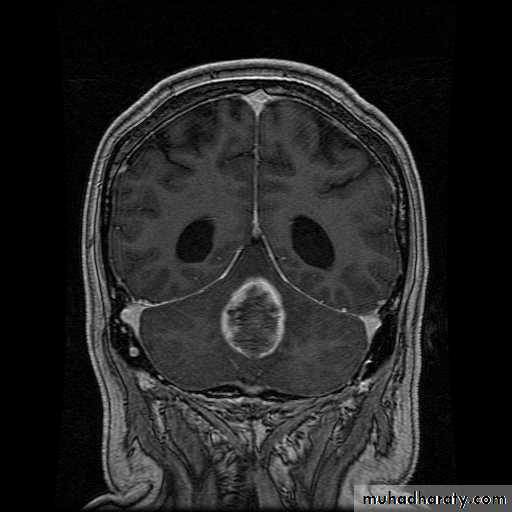

EPENDYMOMA CORONAL MRI